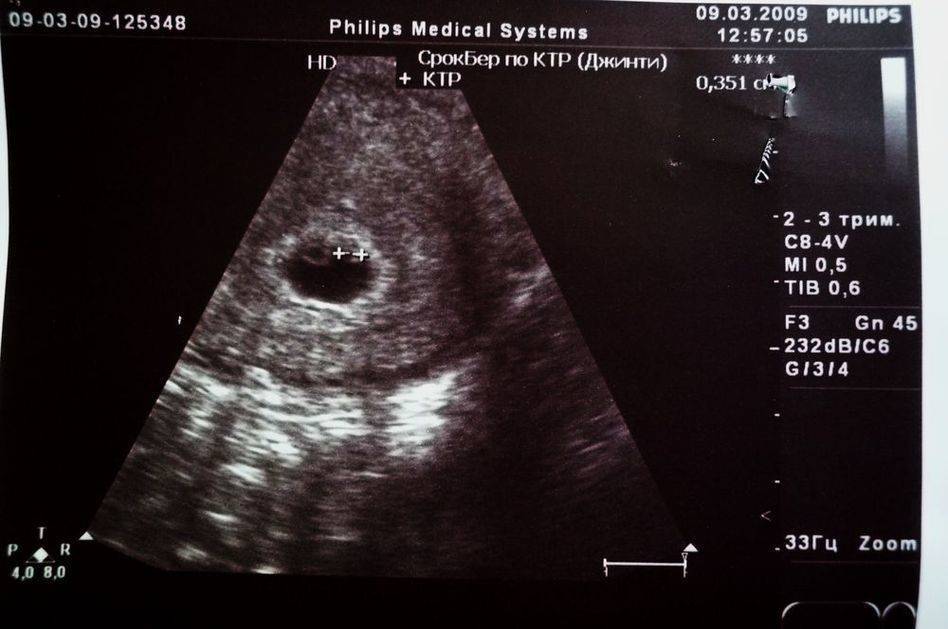

Если у женщины на ранних сроках постоянно болит под пупком, боли нарастающие по интенсивности, иррадиирующие в ногу, подреберье, прямую кишку, гинеколог, в первую очередь, отправит ее на УЗИ, чтобы убедиться, что плодное яйцо находится там, где ему положено, в полости матки.

УЗИ — основной способ диагностики при беременности

Во время беременности врачи сильно ограничены в возможностях диагностики. МРТ запрещено почти во всех случаях, а рентген и КТ желательно выполнять только в исключительных ситуациях. Остается – УЗИ, но проводить его можно не слишком часто. Правильный внимательный гинекологический осмотр и лабораторные анализы остаются одним из лучших решений для выявления болезней.